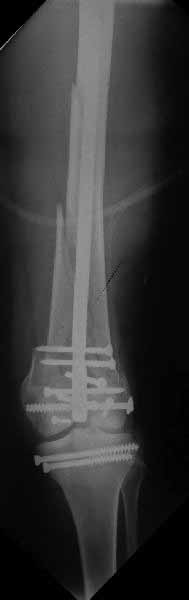

У больных как в этом случае, с вовлечением двух мыщелков правильно, что сделали вытяжение до операции. Здесь имеется флексионный компонент на другой стороне, и я бы рекомендовал операцию делать из двух доступов. Сперва фиксировать медиальную колонну custom made пластиной, обычно 1/3 тубулярной пластиной в 4.5 мм, потому что пока производители опаздывают с медиальной пластиной.

Пластину надо устанавливать на апексе перелома, иначе фрагмент начнет сползать. А на второй стороне, если имеется большой одиночный фрагмент тогда проблем не бывает, и их можно собрать компрессирующими винтами. Проблема наступает тогда когда многофрагментраность на латеральной стороне, где надо применить комбинированный метод, иногда несколькими пластинами. Или сменой позиции установки пластины, чтобы максимально прикрыть перелом и создать боковую поддержку.

Здесь пример медиальной пластины и латеральный комбинированный метод (у второго больного старый перелом тибиал плато, леченный где то и когда то)

наружный мыщелок не дорепонироавн - это приводит к вальгусной деформации оси коленного сустава, очень критично для последующей функции.